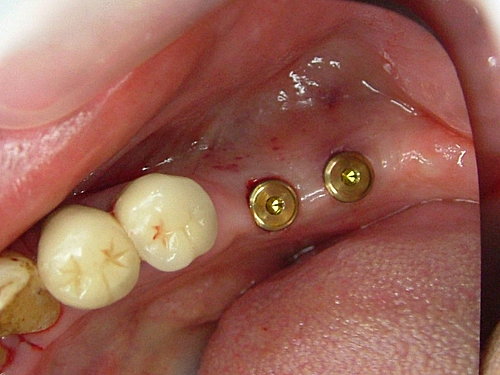

植牙術後看起來的樣子 ..... 不影響日常作息 ....

後牙因條件良好 採不翻瓣一接段植牙術式 (Flapless procedure) ....